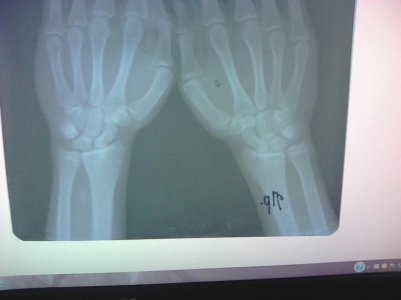

Здравствуйте. Скажите, пожалуйста, закрыты ли зоны роста на следующих снимках? Врач-эндокринолог сказала, что закрыты, но судя по прочитанным мною форумам врач может ошибаться. Врач-рентгенолог про зоны роста ничего не написала, только написала "костный возраст: 18-19 лет." Мне 18 лет, мой рост 161 см. Рост родителей: 152 см и 171 см. По направлению врача сдавал анализы на гормоны - всё в норме.